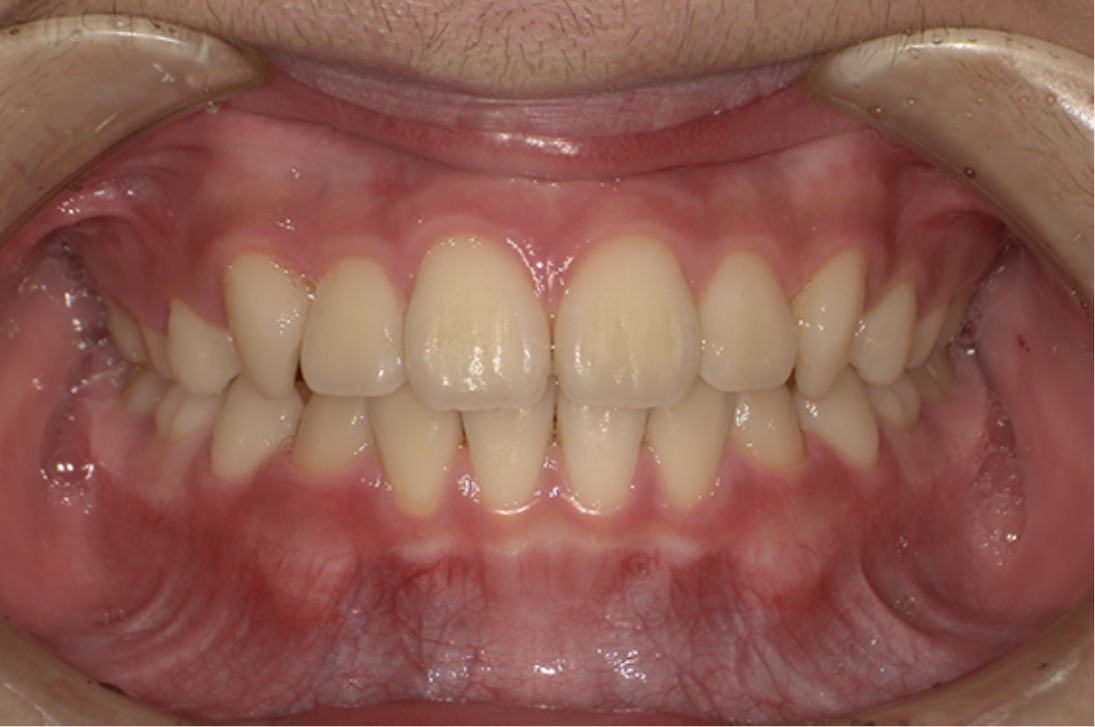

• 治療前

• 治療後

主訴:前歯が出ている

診断:叢生、上顎前突

治療内容:唇側矯正治療

年齢:22歳

治療に用いた装置:マルチブラケット装置

抜歯or非抜歯:抜歯(上下顎両側小臼歯)

期間:20ヶ月

回数:20回

費用:990,000円(税込)

リスク・副作用:虫歯、歯肉炎、歯肉退縮、歯根吸収、後戻りなど